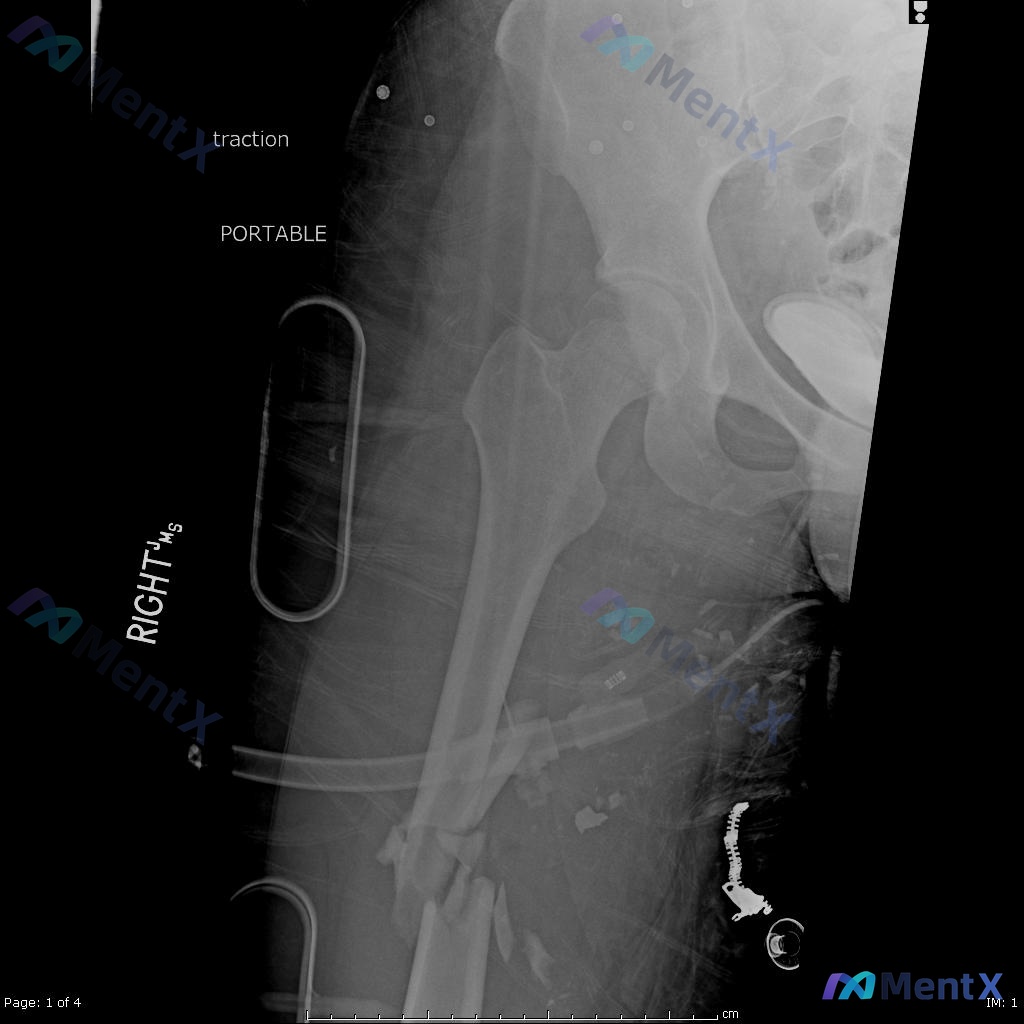

- 术前(图A/B):右侧股骨干中段粉碎性骨折,多块游离骨块,移位明显;局部软组织肿胀;髋膝关节结构未见明显异常